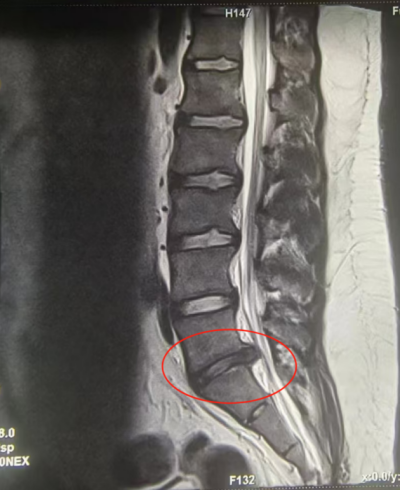

核磁共振影像学显示L5/S1段椎间盘明显膨出

“患者入院时,已经痛得直不起腰来,询问病史才得知,三年前曾因腰痛就医,已诊断为腰椎间盘突出。”主管医生史强介绍,通过一系列影像学检查,核磁检查结果显示腰五骶一椎间盘膨出。经与家属沟通,为高麟选择做骨盆牵引+卧床休息、药物控制、TDP、中药贴敷等理疗的方式保守治疗,经过3天的治疗,高麟表示腰痛情况有了较大缓解,顺利出院。